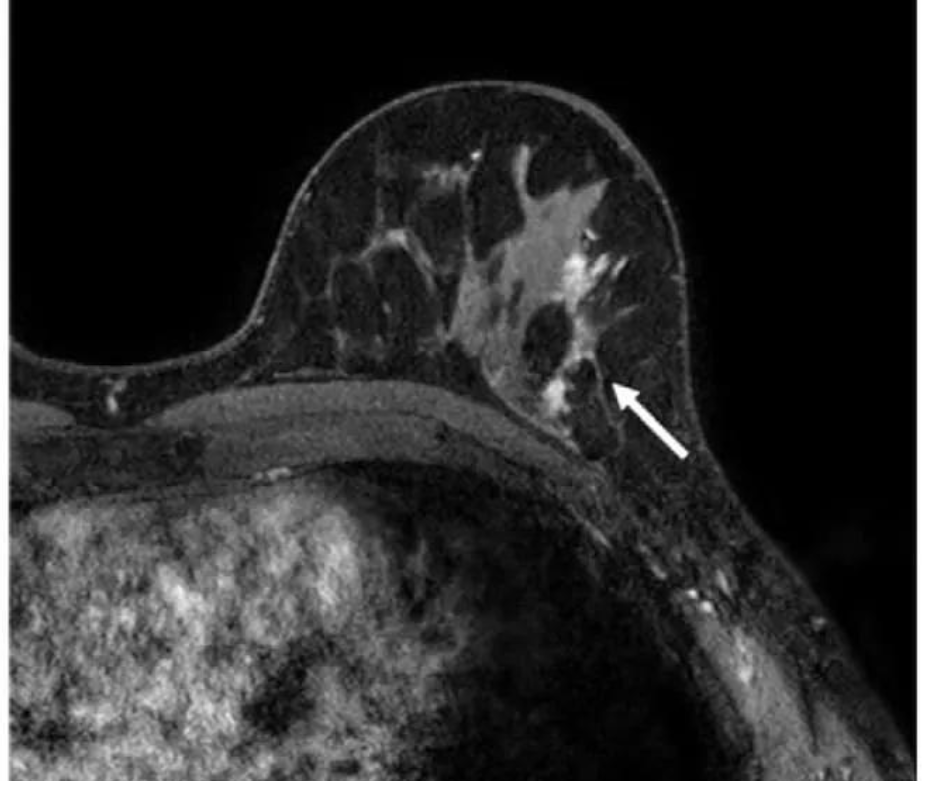

Researchers found that abbreviated breast MRI had a 57 percent higher sensitivity rate for breast cancer (96 percent) than digital breast tomosynthesis (DBT) (39 percent) in a study of 1,444 women with heterogeneously dense or extremely dense breasts. (Image courtesy of Radiology.)

3. Researchers found that abbreviated breast MRI had a 57 percent higher sensitivity rate for breast cancer (96 percent) than digital breast tomosynthesis (DBT) (39 percent) in a study of 1,444 women with heterogeneously dense or extremely dense breasts. The study authors also noted that DBT had a 10 percent higher specificity than abbreviated breast MRI (97 percent vs. 87 percent) and a 17 percent higher positive predictive value (PPV) (36 percent vs. 19 percent).